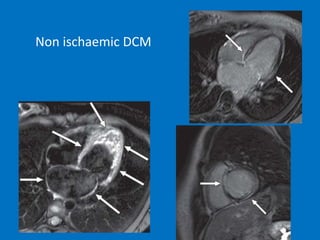

MRI

• black blood images: enlarged cardiac chambers

and thin myocardial walls

• Cine images: show LV hypokinesia, increased

volumes, (end-diastolic volumes that constitute a

dilated CMP: > 140 mL for the LV and > 150 mL

for the RV

• Phase-contrast sequences: impaired diastolic

function. transvalvular flow may be characterized

by a restrictive pattern

• Late gadolinium-enhancement

Non ischaemic DCM

MRI • black bloodimages: enlarged cardiac chambers and thin myocardial walls • Cine images: show LV hypokinesia, increased volumes, (end-diastolic volumes that constitute a dilated CMP: > 140 mL for the LV and > 150 mL for the RV • Phase-contrast sequences: impaired diastolic function. transvalvular flow may be characterized by a restrictive pattern • Late gadolinium-enhancement